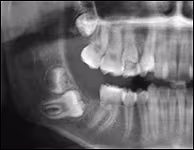

A 14-year-old Caucasian female was referred by her orthodontist with a non-expansile radiolucent lesion associated with impacted tooth #31.